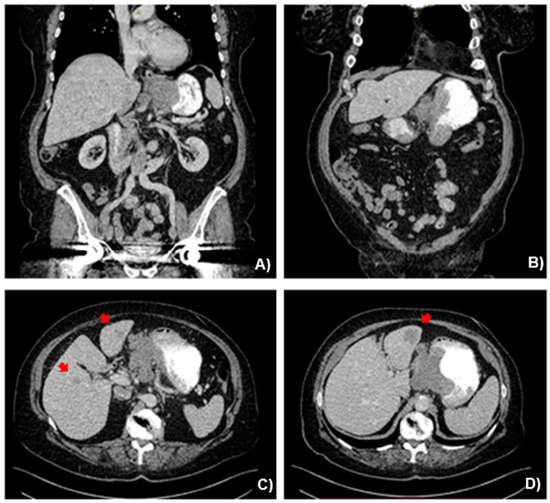

After the completion of a total of six cycles of chemotherapy, the re-staging CT showed major remission of the primary tumor and the metastatic sites (Figure 4). The imaging was complemented with FDG PET-CT and MRI-Liver (Figure 5). High SUV was noticed solely at the EGJ on the FDG PET-CT (Figure 5A). Out of the known hepatic lesions initially present, two were not visible on MRI and one had significantly reduced in size (from 2.6 to 0.7 cm) (Figure 5B). There was also major remission of the patient’s bulky lymph node packet at the lesser curvature. Gastroscopy findings following the completion of induction chemotherapy depicted a significant tumor remission with a single ulcer at the gastric cardia (Figure 6). Given the significant tumor response after induction chemotherapy, with the sole presence of residual active tumor exclusively at the EGJ together with the good performance status of the patient, a conversion surgical resection was recommended. Following MDT discussion, the patient was finally considered eligible for radical surgical resection, in which we decided to include surgical local management of all previous liver metastatic sites. The patient underwent an extended total gastrectomy with D2 lymph node dissection together with metastasectomy of the remaining liver metastatic lesions through an atypical left hepatectomy along with radiofrequency ablation (RFA) of a single scar tissue on the right liver, which was spotted at the site of previous hepatic metastasis and was evaluated using intraoperative liver ultrasound. Intraoperative images along with the image of the resected surgical specimen are shown in Figure 7.

Figure 4. (A,B) Abdominal CT in coronal and (C,D) axial views after induction chemotherapy depicting significant tumor remission compared with the initial staging.